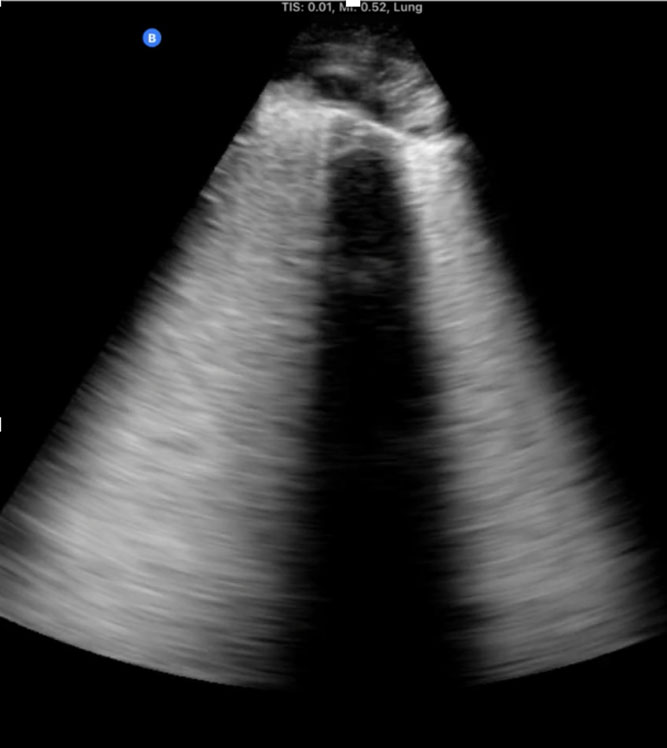

A 6-month-old infant is rushed through the emergency room directly into the Pediatric Intensive Care Unit (PICU) at the Mother and Child Hospital of N'djamena in Chad, Africa. His chest is barely rising with each rapid, shallow breath. A physical examination reveals diminished breath sounds on the left and an oxygen saturation of 80%. Despite being one of the largest hospitals in Chad, it has no portable X-ray machine available. One of our team members on this expedition to Chad brought a personal handheld ultrasound device (iQ, Butterfly Network, Inc, Guilford, CT, USA). Urgently, we performed a point-of-care-ultrasound (PoCUS) evaluation using a left midaxillary and subcostal views, which revealed a huge pleural effusion that was compressing the left lung. Pleurocentes is was guided by the handheld ultrasound, with an almost immediate resolution of the child's respiratory distress. An inspection of the thick fluid drained suggests that the likely cause was tuberculous pleural effusion (TPE).[1]

First-hand experience of recent expeditions to low-resource countries (eg, Chad and Sudan), as well as conflict zones such as the Ukrainian front lines following the Russian invasion on February 2022, reveals the substantial clinical utility that PoCUS may have, particularly when other imaging modalities are unavailable. During a recent expedition to Chad, a portable handheld ultrasound device directly assisted in making critical diagnoses and performing life-saving interventions in several men, women, and children. In total, 12 patients (mean age 14.9 years) were managed with the aid of PoCUS with the most common scenarios being trauma after motor vehicle accidents, respiratory failure, and obstetric complications. The most frequent study types performed were the Extended Focused Assessment with Sonography in Trauma (eFAST), cardiac, and lung studies. Within this group of patients, 2 died within this period (a 13-year-old girl with intra-abdominal perforation who traveled for 5 days to the hospital and a 12-year-old extremely malnourished girl who arrived in severe shock and required immediate CPR), and 2 remained with unknown outcomes but carried grave prognoses. PoCUS directed management in 75% of patients, including pulmonary edema in a laboring woman, an amoebic liver abscess diagnosis and ultrasound-guided drainage in a 3-year-old girl, a diagnosis of large pericardial effusion in a 10-month-old boy with Trisomy 21, and the diagnosis of intracranial hypertension using ocular ultrasound in an unconscious 13-year-old involved in a car accident as a pedestrian, suggesting intracranial bleeding.